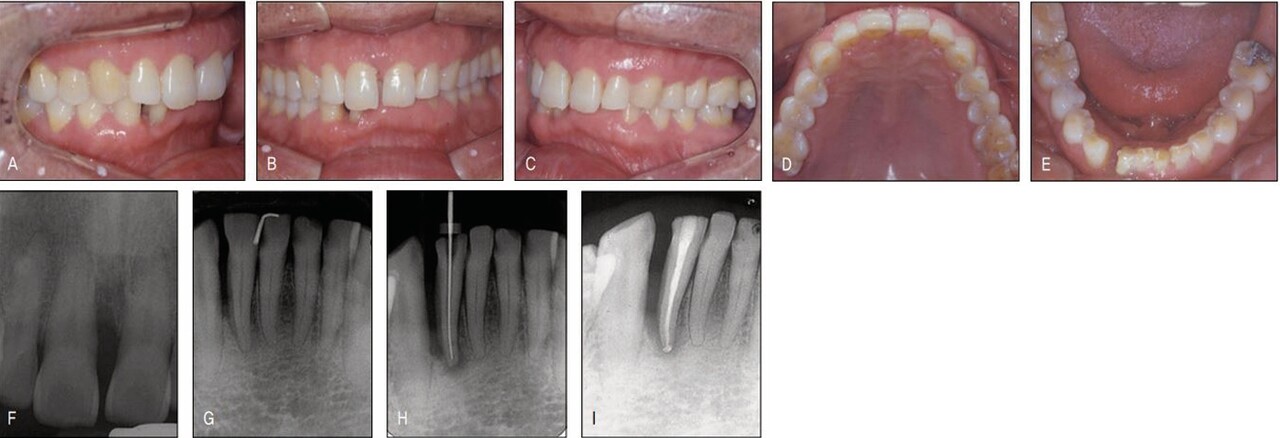

지난 일년 전 하악우측 측절치의 치주 및 근관 치료 중 갑작스럽게 치아가 전위되면서 원심부에 공간이 발생한 환자로, 보철을 위해서는 공간재분배가 불가피하여 교정 치료를 위해 의뢰된 환자였다. 하전치부는 교모와 함께 정출이 나타나 이론적으로는 intrusion 후 보철이 필요하지만 환자는 공간재분배라는 간단한 교정치료 조차 받기를 주저할 정도이어서 치료계획에 넣지도 않았다. 하악의 공간외에 상악정중부에도 치주질환으로 인한 공간이 있어 치료시 하악 상악같이 할 것을 권유하였으나 환자는 보철을 위해 꼭 필요한 하악에서의 교정만 하는 것으로 하고 상악 치료는 거부하였다. 후에 알게 된 사실이지만 환자가 상악교정을 거부한 이유는 장치의 노출 때문이었다. 교정 장치가 보기 싫어서가 아니라 “나이 들어서 교정치료를 받는 것이 민망해서”라고 하였다.

아직도 많은 이들이 교정은 심미목적으로만 치료받는 것으로 잘못 알고 있고, 이에 대한 계몽이 필요하다는 것을 본 증례가 여실히 보여주었다. 과개교합으로 인해 순측부착이 불가하여 설측으로 장치를 부착하였더니 보이지 않는 장치라 환자가 매우 좋아하였다. 한 개의 와이어를 사용하여 간단히 하악교정을 한 후 환자에게 다시 상악 교정을 권유하였더니 환자는 흔쾌하게 상악도 교정을 하겠다고 하였다. 하악에서처럼 심미적 교정장치로 치료 받을 수 있을 것으로 기대했기 때문이었다. 그러나 전치부 과개교합으로 상악설측면에서의 장치 부착이 불가하여 환자에게 투명교정장치를 설명하였고 이 역시 심미적 장치이어서 환자가 수락하고 투명교정장치로 간단하게 공간클로져 교정을 시행하였다.

가철식 장치이어서 다소의 경사이동이 발생하였고 치주질 환으로 우측의 중절치가 더 정출하여 비심미적인 절단연이었으나 스트리핑 그리고 re-shaping 등을 이용하여 심미적인 절단연을 만들어주었다. 교정을 주저하였던 환자는 설측 및 투명장 치 등 심미적 장치로 인해 교정치료 내내 크게 만족해 하였다(그림 23-7~10).